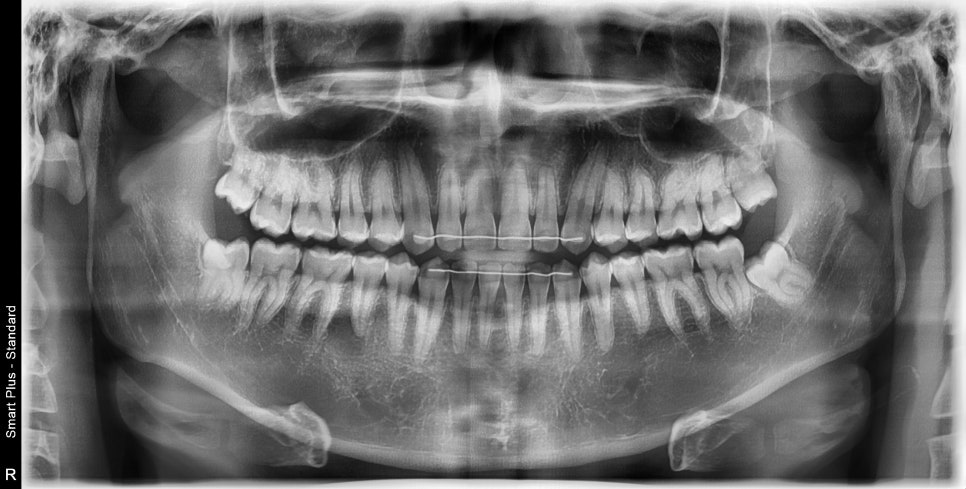

문진, 촉진을 통해 어느 부분이 문제 인지 확인하고, 턱관절이 문제인지 확인을 위해 턱관절 방사선 사진을 찍어봅니다.

위의 사진은 우리가 입을 다물고 벌릴 때, 턱관절의 위치를 확인 위해 찍는 사진입니다.

해당 사진에서 턱관절 쪽으로 이상이 없다고 확인을 하고 근육 쪽의 문제인지 촉진을 해봅니다.